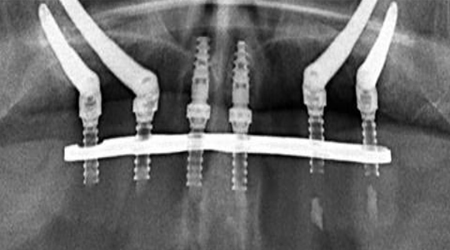

ALL- ON -4 FOR LESS BONE

Upper Jaw/Lower Jaw (Per Jaw)

Technique INR US

4 NOBEL BIOCARE Implants including 2 ANGULATED Implants + IMMEDIATE Provisional Denture + Final Fixed Titanium Hybrid Denture of 12-14 Teeth 350000 5400

4 NOBEL BIOCARE Implants including 2 ANGULATED Implants + IMMEDIATE Provisional Denture + Final Fixed PROCERA Implant Bridge Denture of 12-14 ZIRCONIA Ceramic Crown 500000 7600

ALL- ON -4 WITH ZYGOMA IMPLANTS (FOR MINIMAL BONE)

Upper Jaw

4 NOBEL BIOCARE Implants including 2 ZYGOMA Implants + IMMEDIATE Provisional Denture + Final Fixed TITANIUM HYBRID Denture of 12-14 Teeth 650000 10000

4 NOBEL BIOCARE Implants (QUAD ZYGOMA)+ IMMEDIATE Provisional Denture + Final Fixed TITANIUM HYBRID Denture of 12-14 Teeth 800000 12300